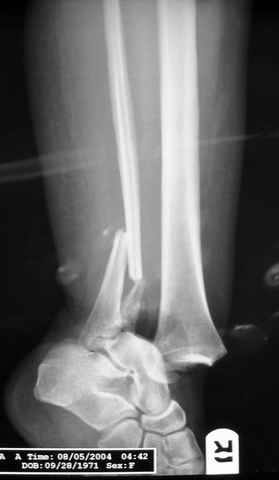

Pilon fracture:

-Появляется ориентир и остов, на чем можно строить восстановление, почему сперва малоберцовую, впервые обьяснили и описали (Pylon type and Ankle fractures) в середине 50х Rienau и Gay.

Восстановливая длину и ротацию малоберцовой кости, затем относительно легче произвести реставрацию остальных элементов перелома дистального эпиметафиза болшеберцовой кости.

где исследования на трупах показали, что малоберцовая кость участвует в стабильности голеностопного сустава, поддерживая наклон тарана (talar tilt) за счет связок. После ознакомления работой Ramsey в ортопедию ввели термин "при переломах голеностопного сустава смещенная

таранная кость следует за малоберцовой костью" т.е. связка не рвется, а тянет таран за собой, поэтому восстановление малоберцовой кости в

первую очередь, затем остальных элементов - стал классическим при лечении данной патолгии. Латеральная колонна (столб), дистальный

конец малоберцевой кости, к нему прикрепляется латеральный суставной фрагмент дистального эпиметафиза большеберцовой кости (как на снимке)

и таранная кость, которые при репозиции малоберцовой кости репонируются автоматически.

Из работ Ramsey and Hamilton, Yablon et., укорочения на 1мм

малоберцовой кости, уменьшает на 42% контактную поверхность между

малоберцевой и таранной кости, которое в свою очередь приводит к

увеличению давления на остальные части суставной поверхности, что

является предпосылкой раннего артроза.